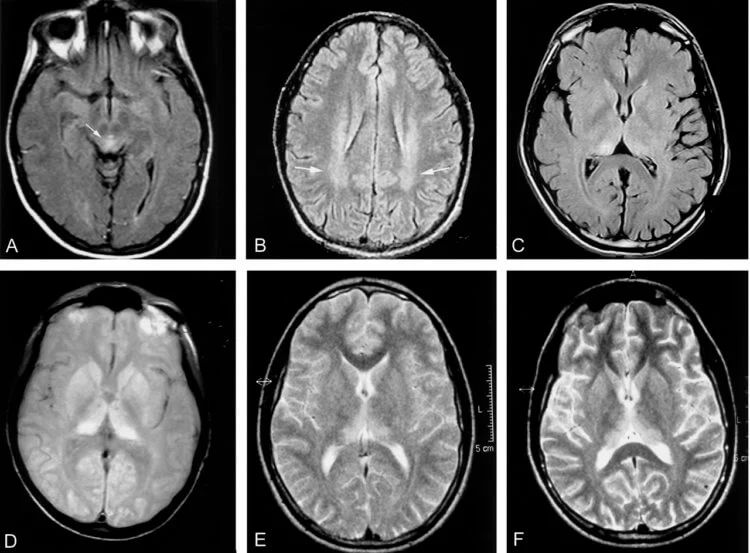

Нейродегенеративные заболевания, вызваны прионами, буквально превращают мозг в губку.

Сканирование мозга пациента с болезнью Крейтцфельдта-Якоба.